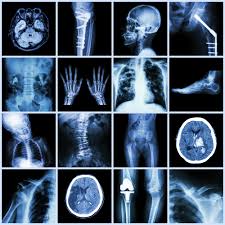

An X-ray is a form of electromagnetic radiation that creates images of the inside of the body to diagnose conditions like fractures and pneumonia.

A CT scan a medical imaging technique that uses X-rays and a computer to create detailed, cross-sectional images (slices) of the body's internal tissues and organs.